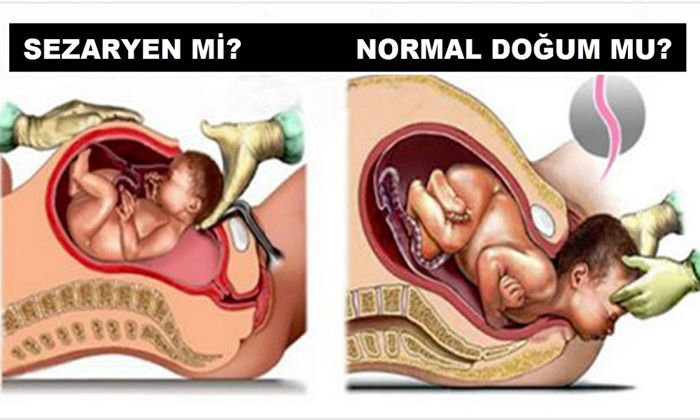

Anne istegiyle sezaryen

Normali normal dogum… Sezaryenin de hayat kurtarma operasyonu oldugunu hatirdan çikarmamak gerekli… Peki ya tibbi bir endikasyonu yani gerekçesi olmadan, sadece annenin istegiyle sezaryen olanlar? Bu konu sayfalarca tartisilabilecek bir konu.. Tartisiliyor da.. Bir de bu isin tibbi boyutu var.. Sonuçta, sezaryen de bir ameliyat ve avantajlari oldugu kadar dezavantajlari da var.

Ben bu yazida, anne istegiyle sezaryeni tibbi açidan ele alacagim.

Anne istegiyle sezaryen ne demektir?

Anne istegiyle sezaryen, annenin, vaginal dogum yapmamasini gerektiren tibbi ya da obstetrik endikasyonlarin yoklugunda, ilk dogumunu sezaryenle yapmasina verilen isimdir. Hastanin tibbi kararlarin verilmesine aktif olarak katilma hakkindan dolayi, son zamanlarda oldukça yayginlasmis bir uygulamadir.

Planlanmis sezaryenin olasi dezavantajlari

Hastanede yatma ve dogum sonrasi iyilesme süreçleri, sezaryenle dogumda vaginal doguma göre tipik olarak daha uzundur. Normal dogum yapan bir anne dogumdan sonra ayaga kalkip bebegiyle ilgilenebilecekken, sezaryen olan bir annenin bebegiyle birlikte kendisinin de birkaç gün bakima ihtiyaci olacaktir. Maternal morbidite de sezaryen dogumla daha yüksektir. Çalismalarda, postpartum kardiyak arrest, yara yeri hematomu, histerektomi, majör puerperal enfeksiyon, anestezi komplikasyonu gibi durumlarin riskleri sezaryen grubunda daha yüksek bulunmustur. Yenidoganin solunum sikintilari (respiratuvar distres sendromu, yenidoganin geçici tasipnesi) gibi durumlarin elektif sezaryen sonrasi vaginal doguma göre daha sik görüldügü bulunmustur, bu durumlar bebegin hastanede yatis süresini uzatabilir.

Anne istegiyle sezaryen olmayi planlayan hastalarin, ilerideki gebeliklerinde bebegin esinin asagida yerlesmesi (plasenta previa), bebegin esinin rashim duvarina gömülmesi (plasenta akreata), artmis rahim yirtilmasi riski, birden fazla karin ameliyati geçirmis olmaya bagli riskler (bagirsak hasari) gibi olumsuz durumlarin risklerinin artmis oldugunu göz önünde bulundurmasi gerekir.

Planlanmis sezaryenin olasi yararlari

Planlanmis sezaryenin tarihi siklikla önceden belirlenmistir. Bu, isle, evdeki diger çocugun bakimiyla ve annenin ihtiyaç duyabilecegi yardimla ilgili ayarlamalari yapabilmesine olanak verir. Planlanmis sezaryenler siklikla 39 – 40 haftalar arasinda gerçeklestirildiginden bebek günasiminin bebekle ilgili risklerinden korunmus olur. (Ancak hedef günasiminin risklerinden bebegi korumak ise, dogum indüksiyonunun da mantikli bir seçenek oldugu unutulmamalidir).

Planlanmis sezaryen durumunda dogum sonu kanamalar planlanmamis (acil) sezaryenlere ve vaginal dogumlara göre daha az görülür. Dogum sonu kanamalarin en sik nedeni uterin atoni (rahimin kendi kendini toplayip kanamayi durduramamasi) ve plasentanin parçalarinin rahim içinde kalmasidir ve planlanmis sezaryenle bu risk faktörleri en aza indirilebilir.

Planlanmis sezaryen, acil sezaryene göre birçok bakimdan daha az risk tasir. Bu risklerin arasinda, enfeksiyon, iç organlarda yaralanma, histerotomi esnasinda fetusun zarar görmesi, kanama ve anestezi komplikasyonlari sayilabilir.

Dogum sancilari baslamadan önce gerçeklestirilen sezaryen dogum, vaginal dogum sürecine bagli morbidite ve mortaliteyi (sakatlik ve ölüm), örnegin omuz takilmasi, sinir hasarlari, kemik travmalar, bebegin dogumda oksijensiz kalmasi gibi, azaltabilmektedir.

Perineal hasar ve üriner – fekal inkontinans gelisecegi korkusu, annelerin vaginal dogum yapmak yerine sezaryeni tercih etmesinin en önemli nedenlerindendir. Ancak bu endiseler bilimsel kanitlara ve çalismalara dayanmaz. Planlanmis sezaryen dogum sonrasi ilk aylarda idrar kaçirma orani daha düsük olsa da, bu oran iki – bes yil içinde vaginal dogum yapan hastalarda benzer olmaktadir. Ayrica, anne istegine bagli sezaryen dogum, uzun vadede üriner ve fekal inkontinanstan (idrar ve gayta kaçirma) koruyor gibi görünmemektedir.